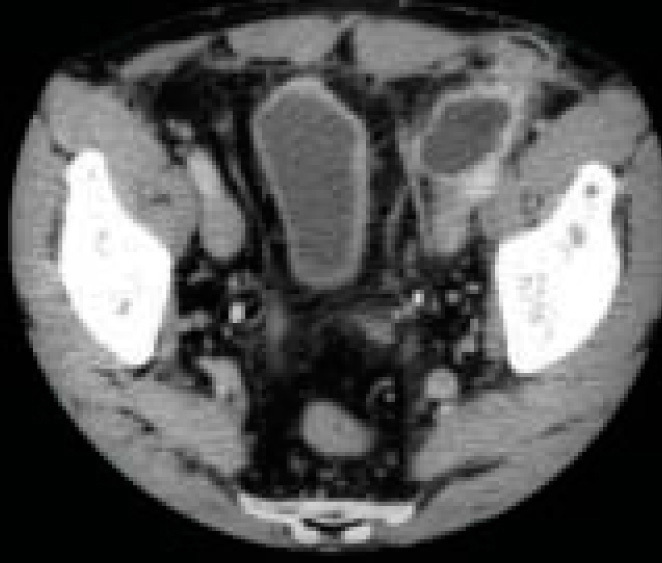

Tomodensitométrie abdominale. Douleurs inguinales après pose d'un plug. Mise en évidence d'un abcès au contact du plug. Voir : Rohr S, Steinmetz JP, Brigand C, Meyer C. Diagnostic et complications des hernies de l'aine. Rev Prat 2003;53(15):1645-50.